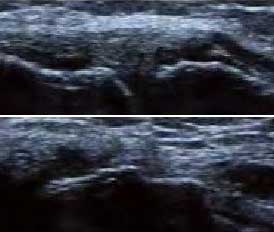

2、清晰显示滑膜异常形态,定量评估RA炎性

类风湿性关节炎以滑膜炎为基本病理改变,超声可观测到关节暗区的范围及厚度,判断有无滑膜增厚、显示不同程度的滑膜均匀或不均匀增厚,分辨滑膜呈绒毛状、团状或结节状结构向关节腔突起的形态。通过对滑膜厚度、水肿、炎性细胞浸润状况的分级、定量评估RA关节内滑膜的炎性程度。

Ⅰ级滑膜增生

轻度滑膜增生,不超过骨面 点连线

Ⅱ级滑膜增生

滑膜增生超过骨面 点连线,呈绒毛状,但不越过骨干

Ⅲ级滑膜增生

滑膜增生超过骨面 点连线,呈团块状延伸超过一侧骨干